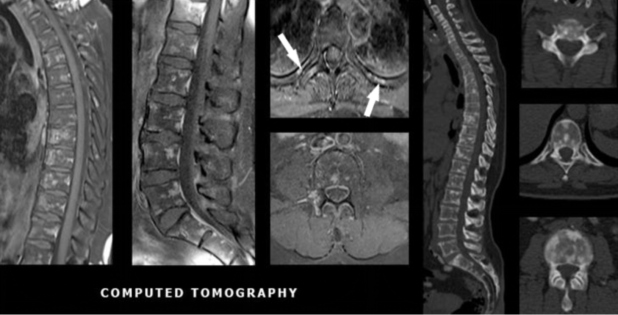

Tomografia computadorizada de tórax (fig. 2) e ressonância magnética (fig. 3), evidenciaram múltiplas formações nodulares ósseas aleatoriamente distribuídas em arcos costais e corpos vertebrais torácicos e lombares, sem sinais de fraturas patológicas. Biópsia (fig. 4) e estudo imunohistoquimico (fig. 5) foram realizados; a análise histológica revelou medula óssea com celularidade preservada e sem evidência de malignidade. A imunohistoquímica (IHQ) demonstrou expressão para CD3 e CD20 sem expressão de citoqueratina, sugerindo tecido hematopoiético reacional e excluindo neoplasia secundária.

Como geralmente é clinicamente assintomática, os achados indicativos de OPQ são tipicamente detectados incidentalmente em exames de imagem durante a investigação de outra condição concomitante(1-3). Caracteristicamente, essas lesões são numerosas, pequenas (1-10 mm), homogêneas, escleróticas, circulares ou ovaladas, bem delimitadas, com ausência de destruição óssea(1,4,5,10). Apresentam-se como ilhas ósseas difusas e simétricas, cujos locais mais comuns são as falanges da mão, seguidas por ossos do carpo, metacarpos, falanges dos pés, metatarsos, ossos do tarso, pelve e epífises e metáfises de ossos longos(2,3,8).

O principal diagnóstico diferencial são metástases osteoblásticas. Neste caso, posto que a paciente era portadora de carcinoma invasivo de mama, essa foi a primeira hipótese aventada. Porém, análises posteriores fortaleceram a possibilidade de uma condição benigna em detrimento a metástases neoplásicas. Em relação ao câncer de mama, até 70% das metástases são esqueléticas, podendo apresentar aspecto radiológico lítico, blástico ou misto(7). Em contraste à OPQ, as lesões metastáticas osteoblásticas tendem a ser assimétricas de tamanhos variados e a apresentar destruição óssea e reação periosteal(3,4,7). São vistas com maior frequência em costelas, corpos vertebrais e diáfises de ossos longos(1-3). Outros diagnósticos diferenciais da OPQ incluem mastocitose e esclerose tuberosa. Em ambas estas condições, as lesões tendem a apresentar menor preferência metafisária e epifisária e a ser mais assimétricas e mal definidas(3,6).